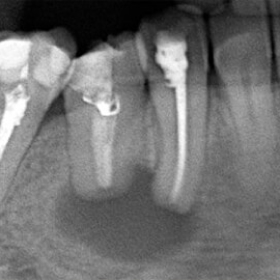

Лечение кисты зуба кальцием отзывы Главная задача при лечении кисты корня зуба - устранить очаг инфекции . Если обратиться к врачу на ранней стадии воспаления, можно обойтись обычным пломбированием каналов .

Пломбировочный материал с кальцием лечение кисты Проблема лечения деструктивных форм хронического периодонтита до сих пор является актуальной и до конца не решенной задачей терапевтической стоматологии .

У меня киста на корне зуба, неделю назад открыла каналы (были боли) и почистила все затихло .Сегодня начала лечение (растворение )кисты кальцием в 10 .00 с 14 .00 на стенку лезу, терпеть нет уже сил .Но врач настаивает потерпеть до утра,была у нее в 19 .00 она обезболила . . .